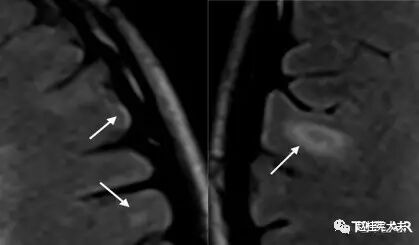

图16. 示C2-6水平颈髓内散在小斑片状T2较高信号,箭头示C4-5水平结节状高信号灶。

图17. 示T5水平胸髓内见短节段椭圆形病灶,T2高信号。

图18. 示T7-8水平胸髓内见条片状T2高信号,且<2个椎体节段。

视神经受侵犯时,呈现T2高信号并可伴视神经增粗,与单纯MS相比,NMO视神经病变范围更广泛,可延伸到视神经后部甚至视交叉,且病变通常呈对称性分布[3];MS脊髓受累者,病灶多>3 mm且<2个椎体节段,横断面上<1/2脊髓面积且水肿轻,而NMOSD脊髓病变可扩展到3个以上脊髓水平,但部分亚洲MS患者的脊髓病灶长度可≥2个椎体节段,AQP4抗体检测有助于鉴别。